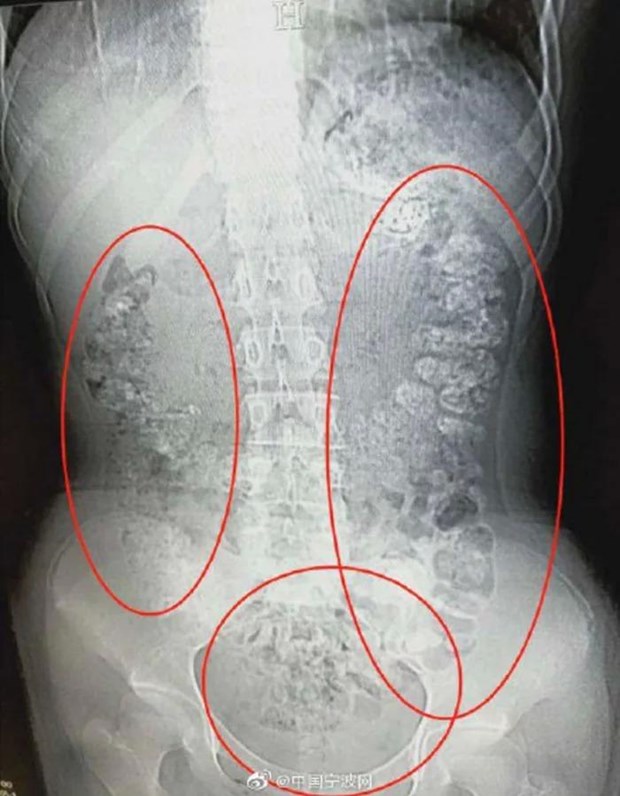

Các hạt trân châu chưa được tiêu hóa hết.

Phát hiện bụng cô bé phình to bất thường, các bác sỹ đã quyết định đưa bệnh nhân này đi chụp cắt lớp. Kết quả chụp cắt lớp cho thấy hàng trăm vật thể nhỏ hình tròn nằm trong khắp các cơ quan nội tạng, từ dạ dày, đại tràng, ruột và hậu môn.

Sau khi cùng nhau thảo luận, các bác sỹ kết luận những vật thể nhỏ này là các hạt trân châu chưa được tiêu hóa hết. Bác sỹ Zhang Louwei đã hỏi cô bé xem bệnh nhân có ăn gì khó tiêu trong vài ngày qua hay không. Cô bé thừa nhận đã uống một cốc trà sữa từ 5 ngày trước khi nhập viện.

Các hạt trân châu vẫn mắc kẹt trong hệ tiêu hóa.